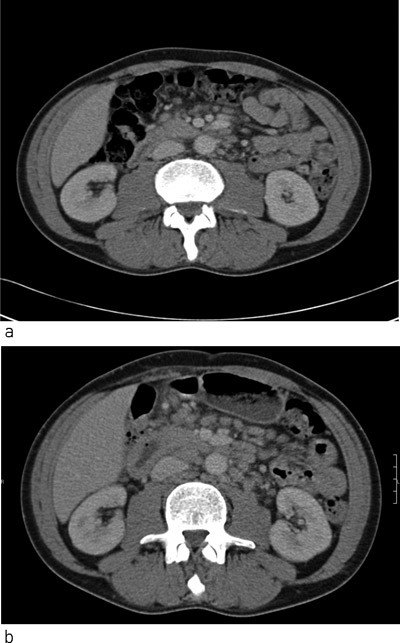

Pasienten. En 46 år gammel mann ble innlagt med nyoppdaget hivinfeksjon og alvorlig immunsvikt, med CD4-tall på 6 · 10⁶/l. Han fikk initialt behandling med høydose trimetoprim-sulfa grunnet pneumoni med Pneumocystis jirovecii. Dette ble seponert pga. utslett og feber rundt 38 °C, men temperaturen gikk ikke ned. Man gjorde omfattende diagnostiske utredninger, inkludert mykobakteriedyrking fra blod og feces, uten å påvise andre opportunistiske infeksjoner. CT abdomen viste imidlertid multiple lett forstørrede glandler paraaortalt. Tre uker etter oppstart av HAART-behandling ble han på nytt innlagt med feber på 39 °C, anemi og vekttap. CT abdomen viste betydelig økning i antall lymfeknuter og lymfeknutestørrelse (fig 1), og man påviste nå Mycobacterium avium-intracellularkompleks i dyrkinger fra lymfeknutebiopsi, blod, beinmarg og feces. Man fortsatte HAART-behandlingen og startet med ciprofloksacin, klaritromycin og etambutol. Etter ti dager var pasienten afebril, med økende vekt og stigende hemoglobinverdi. CD4-tallet var 30 · 10⁶/l. Etter fire måneders behandling var det steget til 100 · 10⁶/l.